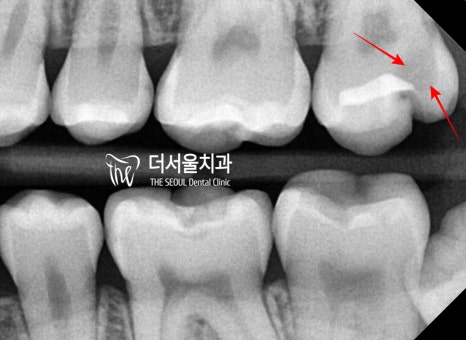

일단, 교익 방사선 촬영(Bite wing)을

먼저 실시 했습니다.

그 결과, 육안검진으로는 보기 힘든

인접면 우식증(proximal caires)가

관찰이 됩니다.

눈으로 봤을 때는

‘이게 충치라고?’ 할 수 있습니다.

근데 교익 방사선 사진에서는

치아 우식증이라는 것을 알 수 있었죠.